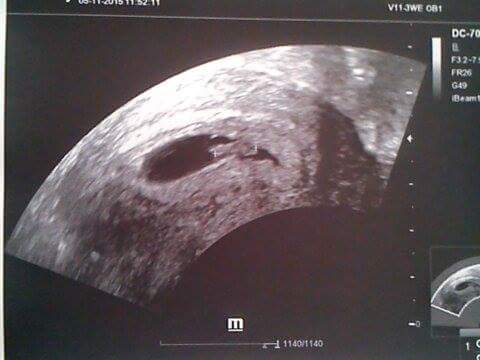

no jinak je takhle příjmená říkala že je tam počínající srdeční akce a šla sem.Je na nic že jdu mě dělají pořád ultrazvuk dnes sem říkala že nechcu az příště a stejně ho udělala že se musí podívat vyplázla sem 50 korun za zrcátko kterým mě rozrýpala akorát a bylo

Petko já sem akorát rozhozena a smutná ....vím na jednu stranu co bych chtěla kdyz me dělají ultrazvuk 2 krát do týdne přesně predtydnem byl pouze gestacni vacek ale copak chcú tak moc když chci slyšet srdíčko přítomno...proto jsem nechtěla aby mě ho dělala protože ultrazvuk byl v pátek a byl gestacnia zloudkovy vacek tak jdu v pondeli.

Co to je jako počínající srdecni akce? Buď je nebo není ne?

Já bych řekla, že ještě třeba není pravidelná nebo dostatečně rychlá.... klídek, vše jde jak má ;)

ahoj holky, já jswm byla na konteole ve čtvrtek, srdíčko bilo krásně vidět, netušila jsem že to jw tak krásný(moje první) jinak 7+0 a první dotečka doma. Další kontrola za 3.týdny a když bude vše ok dostaneme průkazku. Soufám, že Vám to taky všem dobře dopadne

Jinak velikost naěeho puntíka (pracovní název

) byl 9mm